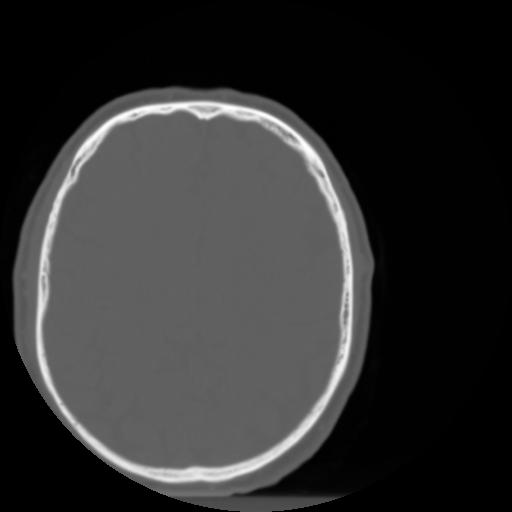

3 CEREBRO,,Axial,3.0,CEREBRO,,